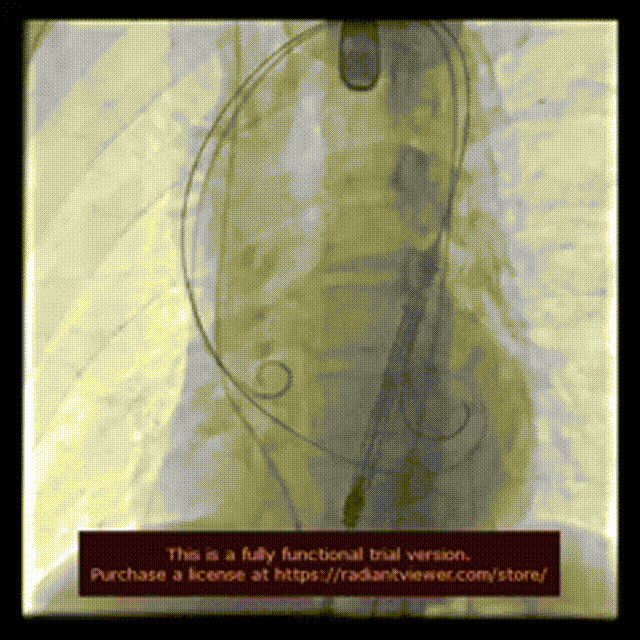

手术过程:

术前造影检查,主动脉瓣大量返流

圈套器辅助下,送入30mmVitaflow瓣膜

造影定位,可见无冠瓣叶较高

快速起搏条件下前期释放2/3瓣膜

造影显示瓣膜位置良好后完全释放

术后造影

数字减影模式检查下肢血管